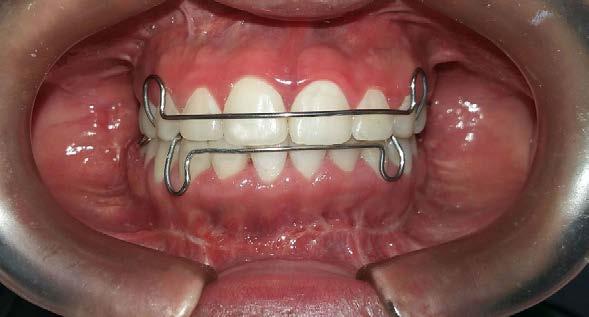

Se planteó la corrección del perfil facial, corrección de las relaciones esqueléticas, corrección de overjet, overbite, del apiñamiento mandibular y cierre de espacio anterosuperiores; obtención de la clase I molar y canina bilateral, realizar las exodoncias de los terceros molares 18, 28, 38 y 48. Se realizó en una fase prequirúrgica de alineación, nivelación, (descompensación dental), tripodismo (estabilidad oclusal) utilizando brackets Roth .022 × .028, bandas en 6's y 7's

superiores e inferiores y vástagos quirúrgicos (Figura 6).

Segunda fase quirúrgica de impactación maxilar Lefort I, 4 mm, (Figura 7), se realizó la cirugía mandibular que consistió en la osteotomía sagital de la rama bilateral de avance, 9 mm (Figura 8), se hizo la cirugía del mentón con la mentoplastía de avance 4 mm, (Figura 9) y una fase postquirúrgica de detallado y retención.

Se colocaron retenedores: Hawley para superior e inferior (Figura 18).